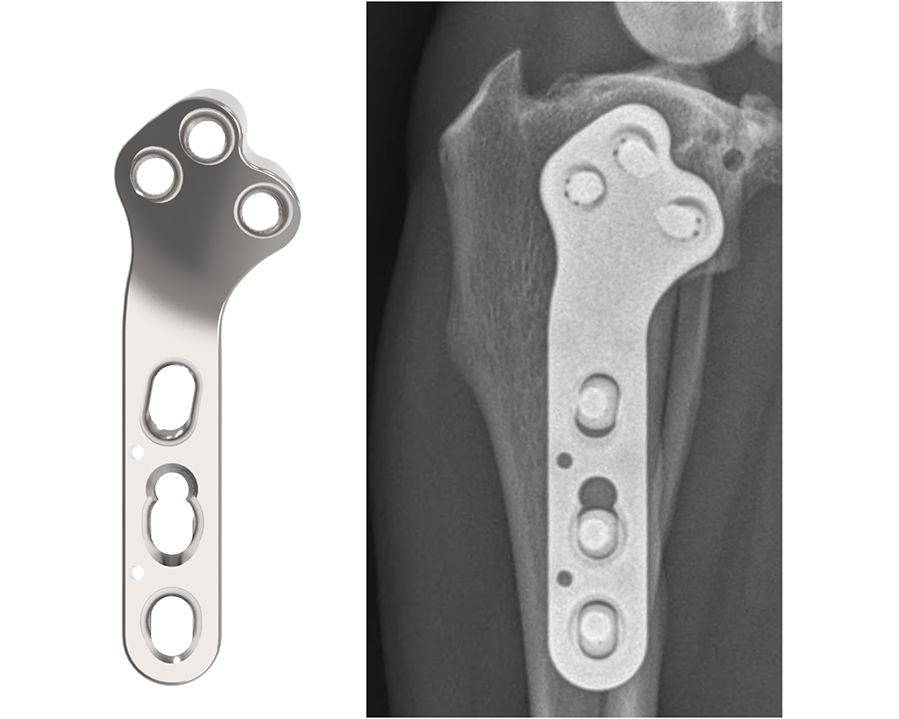

3.5 mm TPLO Plate with Advanced Radial Compression (ARC)

The DePuy Synthes TPLO System is meticulously designed for stabilizing osteotomies of the canine proximal tibia, ensuring stable fixation and reliable healing. Developed in collaboration with and approved by the AO Technical Commission, the ARC TPLO plate comprises two 3.5 mm plates, for both left and right applications.

This innovative system is engineered to deliver precise compression across the osteotomy, leveraging specialized compression holes along the shaft. This targeted compression not only fosters direct bone healing but also bolsters resistance against potential rock-back failures. Moreover, it streamlines the contour of the proximal plate and optimizes screw placements, reducing the necessity for plate contouring while ensuring dependable locking screw positioning. The design features a consistent locking interface between the plate and the locking screws, reinforcing stability and integrity.

The ARC TPLO plate stands out for its continuous, precisely directed compression across the osteotomy site. Notably, the proximal section of the ARC TPLO plate is angled in a slightly more caudal direction to accommodate diverse patient anatomies. Furthermore, the trajectories of proximal locking screws are designed to steer clear of the articular surface while engaging the central mass of the proximal tibia, ensuring optimal fixation and stability.

The newly innovated implant, 3.5 mm TPLO with Advanced Radial Compression (ARC), locates these screws closer to the center of the bone while preserving the clinically‐proven angle of compression.

The ARC TPLO plate provides continuous, controlled, and directed compression across the osteotomy via a unique system of holes that serves to translate and rotate the plate simultaneously during compression. The resultant direction of compression has been designed to match that of the DPS standard TPLO plate, which is clinically proven to provide excellent healing and improved resistance to rock‐back.

Additionally, the proximal section of the ARC TPLO plate is more caudally oriented to provide better anatomical fit on some patients.

And, as with all DPS TPLO plates, the proximal locking screw trajectories are designed to avoid the articular surface and engage the central mass of the proximal tibia.

The ARC TPLO plate comprises two 3.5 mm plates, for both left and right applications.